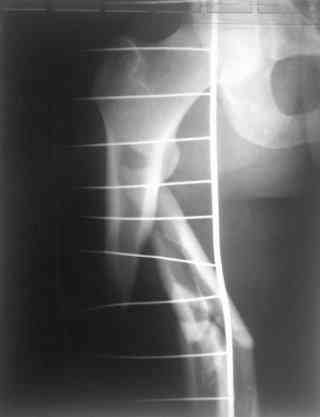

Re: С3-перелом бедра как лечить дальше?....

одна проблема в моей компьютерной неграмотности(не смог прикрепить снимки), а другая в том, что связь с пациентом потеряна и,насколько я понял в своем регионе ему посоветоваться не с кем, кроме главного врача который отреагировал на выбранную нами тактику так: "там тебя использовали в качестве подопытного кролика...".

Надеюсь сейчас показать перелом, а потом синтез.